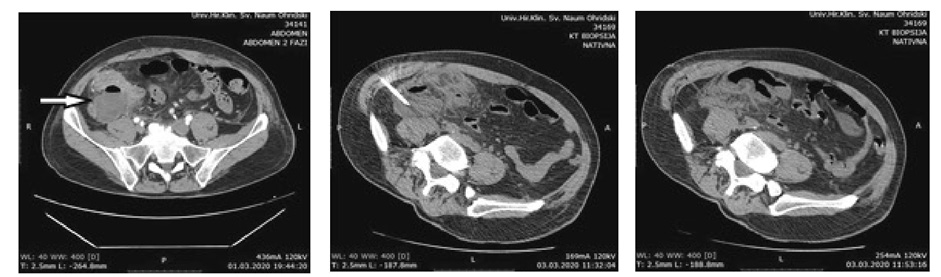

Two patients presented with postoperative pyrexia without the need of any additional intervention. There were no cases of wound infection. One patient was reoperated for early postoperative mechanical bowel obstruction and had uneventful postoperative period. One patient presented with postoperative IAA and it was successfully evacuated and drained by CT guidance (Figure 1).

Figure 1. IAA evacuation and drainage

The IAA treatment can be operative (laparotomy) or with US or CT-guided percutaneous drainage. The minimal invasiveness of the procedure, its efficiency (over 90% successfulness) and no need for general anest­hesia, makes the percutaneous drainage first choice method for post appendectomy IAA. However, it has some limitations when a diffuse interintestinal collections are present [36–38].